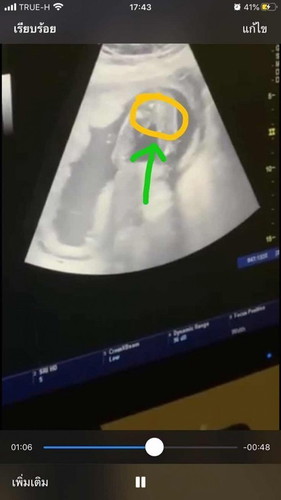

ท้องเกือบ7เดือนแล้ว ส่วนตัวเรารู้สึกว่าลูกเป็นผชมาตลอด แต่ซาว2ครั้งแล้ว(ซาวล่าสุด5เดือนกว่าคะ)คุนหมอก็บอกผญ แม่บ้านไหนเคยเป็นแบบเราบ้างแล้วผลสรุปออกมาตรงกับคุณหมอมั่ยค๊ะ

น่าจะผู้หญิงนะค่ะ เพราะถ้าเป็นผู้ชาย อายุครรภ์ขนาดนี้จู๋ต้องยื่นออกมาชัดเจนค่ะ (บ้านนี้ได้ลูกชายจู๋มาชัดมาก)

บ้านนี้ซาวคลีนิคไม่มีจู๋หมอบอกผญ95%แต่โรงบาลบอกผช100%เห็นจู๋นิดๆเอาไงดีทีนี้😅😅😅

บ้านนี้ไปซาวมาครั้งที่ 2 หมอบอกว่า ผู้หญิง แต่ ไม่มั่นใจค่ะ เพราะน้องหนีบขาค่ะ